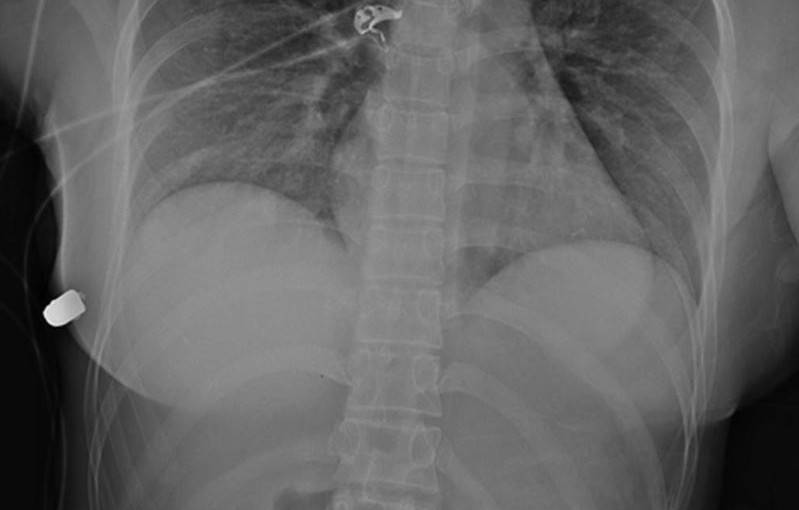

從掃描所得,發現子彈從Journals的左面乳房進入,但被矽膠植入物影響,令子彈轉移至右面乳房,避過直入心臟的危機。

研究表明,基於子彈進入的軌跡,及根據放射學評估,令到子彈出現軌跡偏離的唯一原因,是左面乳房的矽膠植入物。